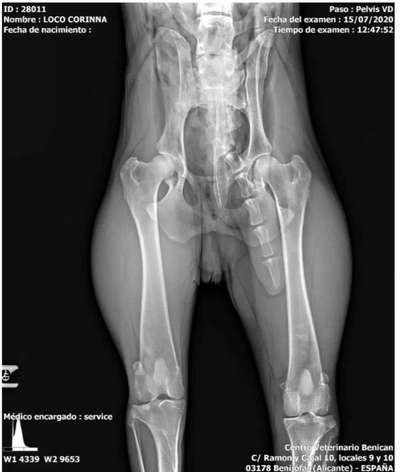

Hallo, ich überlege noch einen Dobermann aufzunehmen. Allerdings hat dieser eine Fehlbildung am Steißbeinwirbel. Wird es den Hund stören? Muss ich mit hohen Behandlungskosten rechnen?